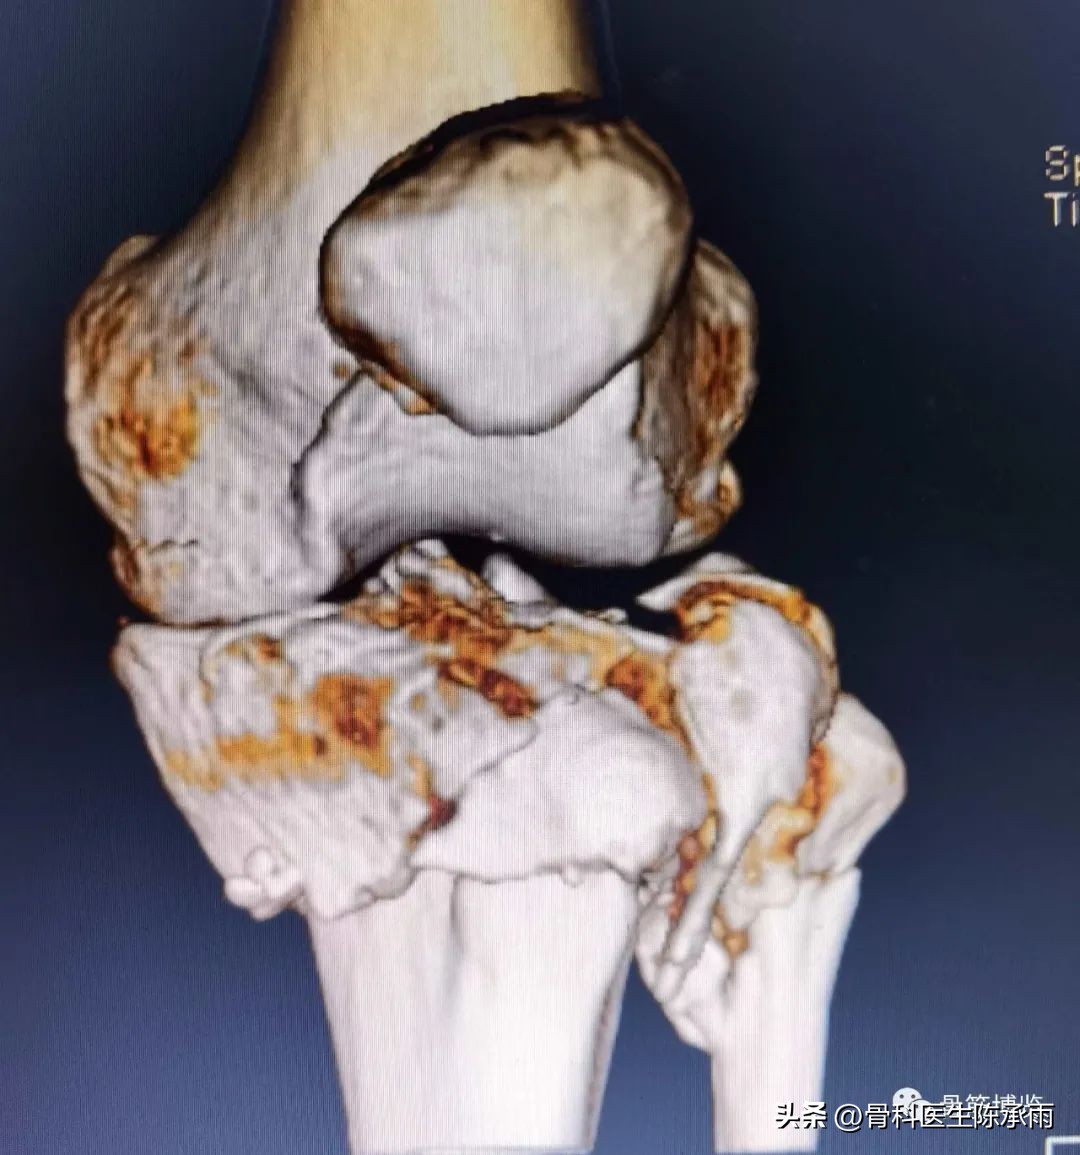

近段时间的胫骨平台骨折,没来得及详细整理

胫骨平台骨折的分型比较多,我们临床上常用的就是Schatzker分型和AO骨折的分型,还有骨折脱位的Hohi-Moore分型,这是我们常用的三个分型。

对AO 分型来讲,现在这是AO推出来更详细的,再分为ABC。随着分型的增加,从A到C骨折的损伤程度是越来越重,治疗也越来越困难,从1到2 ,123也是这个规律,骨折的分型就是给我们表明了骨折的一个损伤的程度,治疗办法和损伤的特点。我们对于骨折脱位的分型,常用Hohi-Moore分型,这个是弥补了,Schatzker和AO分型的一些缺陷。